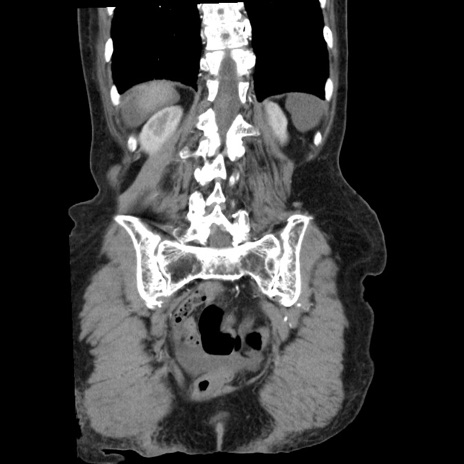

横断像

矢状断像